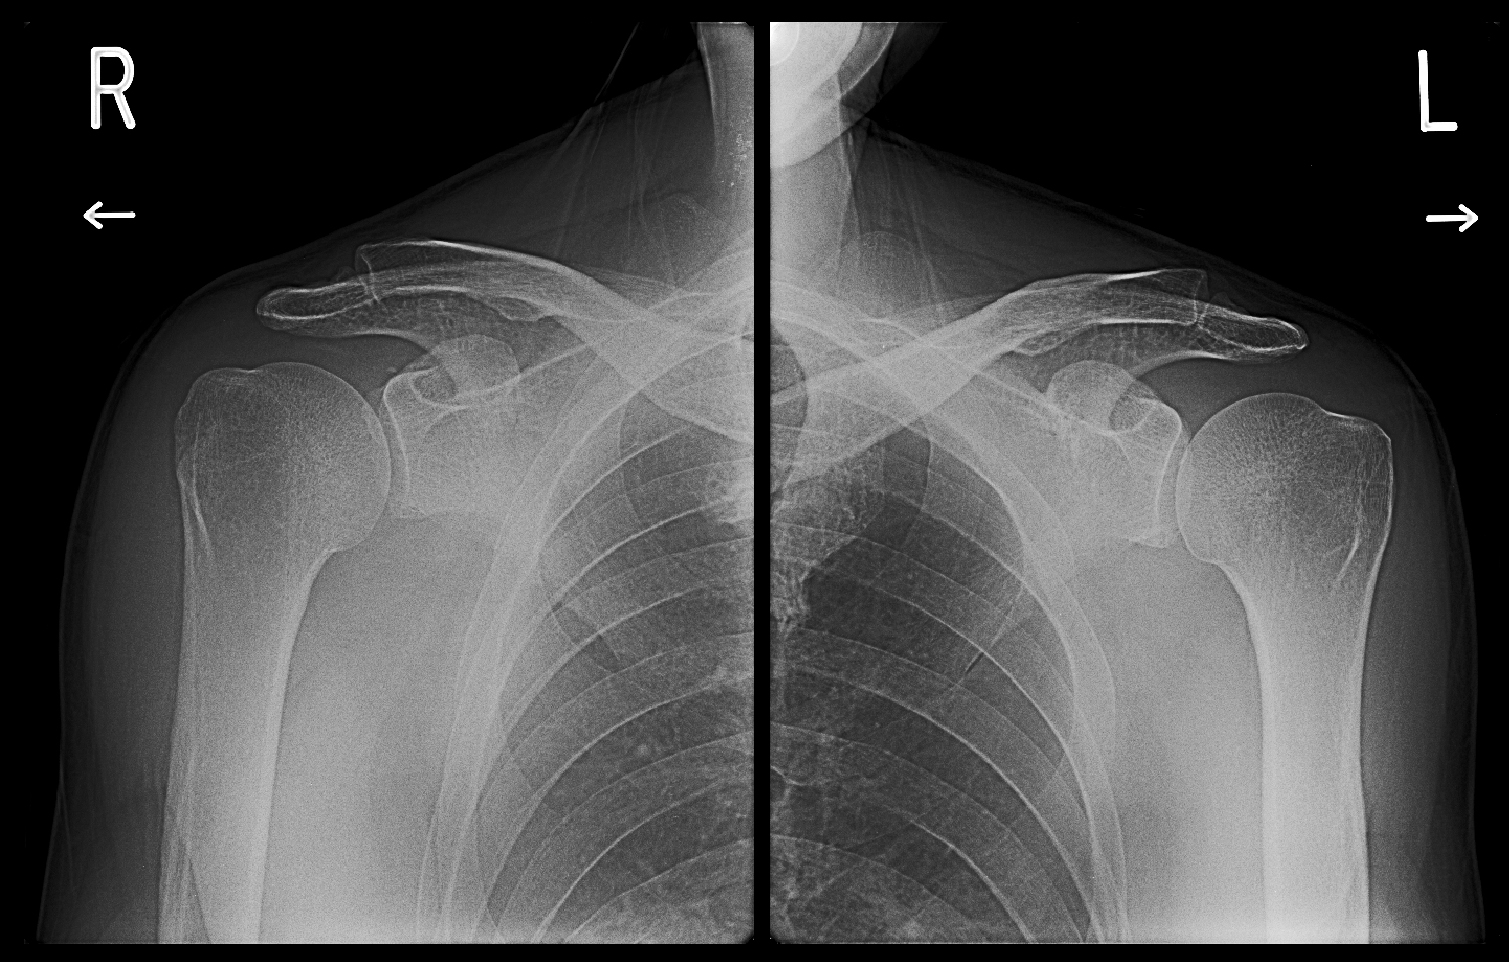

51才の調理師の男性です。平成30年2月27日に右肩痛、3月17日に左肩痛で受診され、ともに局所注射で症状は軽減しました。

56才男 Xp1.jpg